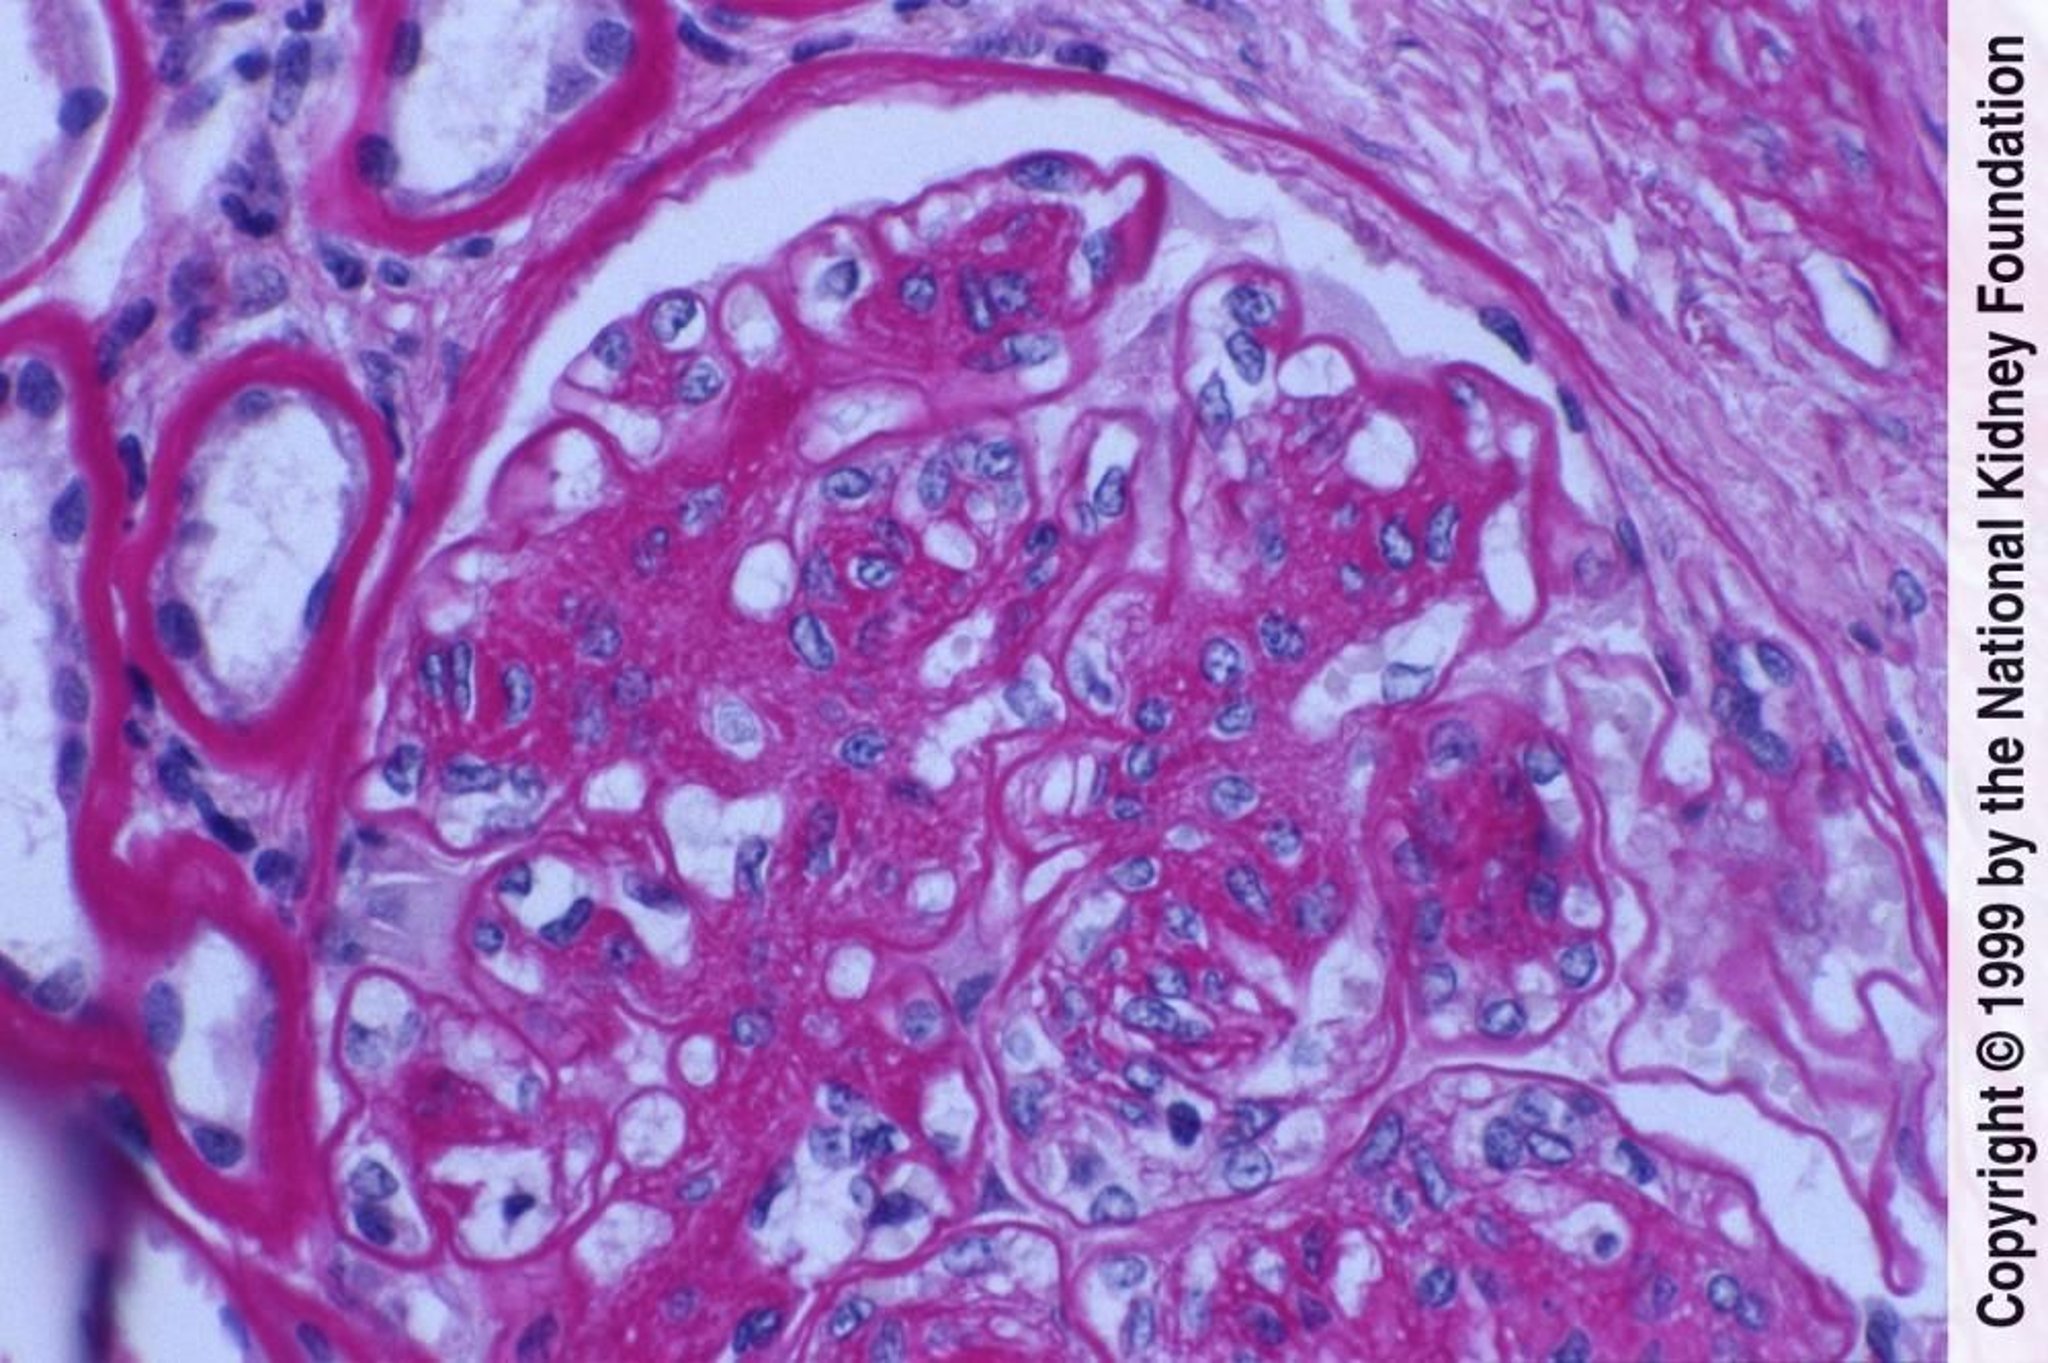

Bệnh thận do tiểu đường (tăng sinh tế bào gian mạch và mở rộng chất nền)

Tăng sinh tế bào gian mạch và mở rộng chất nền kèm theo tổn thương nội mô biểu hiện ở đây là màng đáy cầu thận dày lên mà không có lắng đọng phức hợp miễn dịch rõ ràng (nhuộm axit-Schiff định kỳ, ×400).

Hình ảnh do bác sĩ Agnes Fogo và American Journal of Kidney Diseases' Atlas of Renal Pathology cung cấp (xem www.ajkd.org).